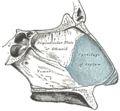

يعتبر الجدار الوحشي أكثر جدران جوف الأنف تعقيداً؛ إذ يساهم في تركيبه كل من العظم الأنفي والغربالي والدمعي والفكي العلوي والصفيحة العمودية للعظم الحنكي والصفيحة الجناحية الأنسية للعظم الوتدي. يتميز الجدار الوحشي ببروز ثلاث تراكيب عظمية تتوضع فوق بعضها تدعى المحارات الأنفية.[1][6] كما يتميز الجدار الوحشي بوجود ارتفاع دائري ينتج عن بروز الخلايا الغربالية المتوسطة نحو الأنسي يدعى الفقاعة الغربالية، وإلى الأسفل والأمام من هذه الفقاعة يوجد ثلم متقوس يدعى الفرجة الهلالية.[6]

يقسم جوف الأنف بواسطة حاجز الأنف إلى قسمين أيمن وأيسر، ويقسم كل منهما بواسطة المحارات الأنفية الثلاثة إلى أربع فسحات هي من الأعلى للأسفل:

- الردب الوتدي الغربالي: يقع فوق المحارة الأنفية العلوية وخلفها.

- الصماخ الأنفي العلوي: يقع تحت المحارة العلوية ووحشيها.

- الصماخ الأنفي الأوسط: يقع تحت المحارة الأنفية الوسطى ووحشيها.

- الصماخ الأنفي السفلي: يقع تحت المحارة الأنفية السفلية ووحشيها.[1]